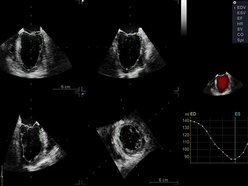

To ogromny krok naprzód. Urządzenie pozwala dokładnie ocenić, jak pracują komory i przedsionki serca, a także szybko uzyskać rzetelne wyniki przy minimalnym wysiłku ze strony operatora – mówi dr Maciej Nadel, kardiolog z Uniwersytetu Medycznego w Łodzi.

Nowy echokardiograf GE Vivid E95 Ultra Edition został wyposażony w specjalną głowicę, która znacząco przyspiesza badania i zwiększa ich dokładność. To szczególnie ważne w kardiologii, gdzie liczy się czas i precyzja. Sprzęt będzie służył zarówno pacjentom trafiającym do specjalistów, jak i naukowcom prowadzącym badania nad nowymi metodami leczenia. To kolejny dowód na to, że łódzka medycyna łączy nowoczesną technologię z troską o zdrowie mieszkańców.